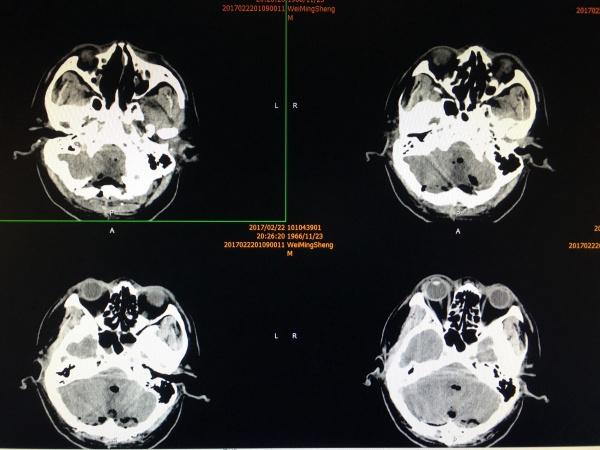

患者中年男性,主诉很是简单,头痛、头晕2月,近期有加重,在外院神内就诊,发现问题后,即刻转至我院,再行头颅MRI检查示:

术前我们考虑手术的难度共有以下几点:1、肿瘤广泛,四脑室、CP角、小脑蚓部、小脑扁桃体均有侵犯。2、需要打开四脑室,全切或次全切肿瘤。3、肿瘤与延髓紧贴,是否有明确间隙,如没有,是否处理延髓上的肿瘤。4、肿瘤范围广,可能肿瘤中已包绕了重要的血管、神经。